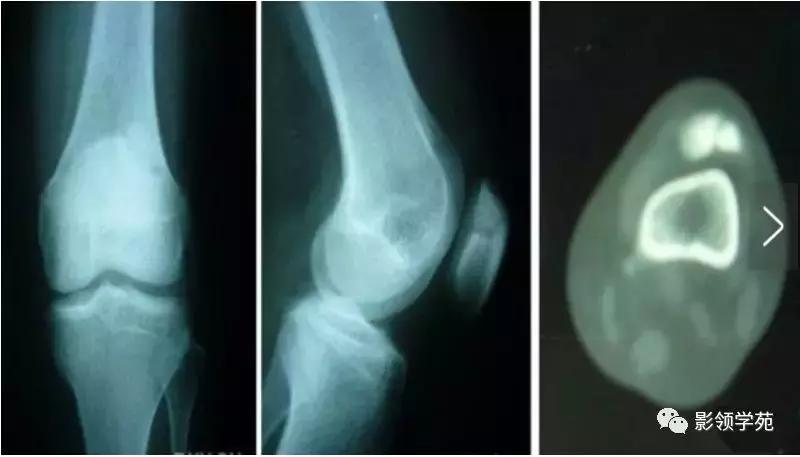

7、剥脱性骨软骨炎

关节内的骨软骨病,病因不明,关节软骨和软骨下骨变性和再钙化,最常见于股骨内髁,模糊的、定位不清的膝关节疼痛,有晨僵,反复的关节内积液(轻度)。如有游离体,可发生交锁症状。股四头肌萎缩,受累股骨髁关节软骨面压痛。

X线平片显示骨软骨病损或关节内游离体。如怀疑剥脱性骨软骨炎,摄片应包括前后位、后前隧道位、侧位和髌股关节切线位。